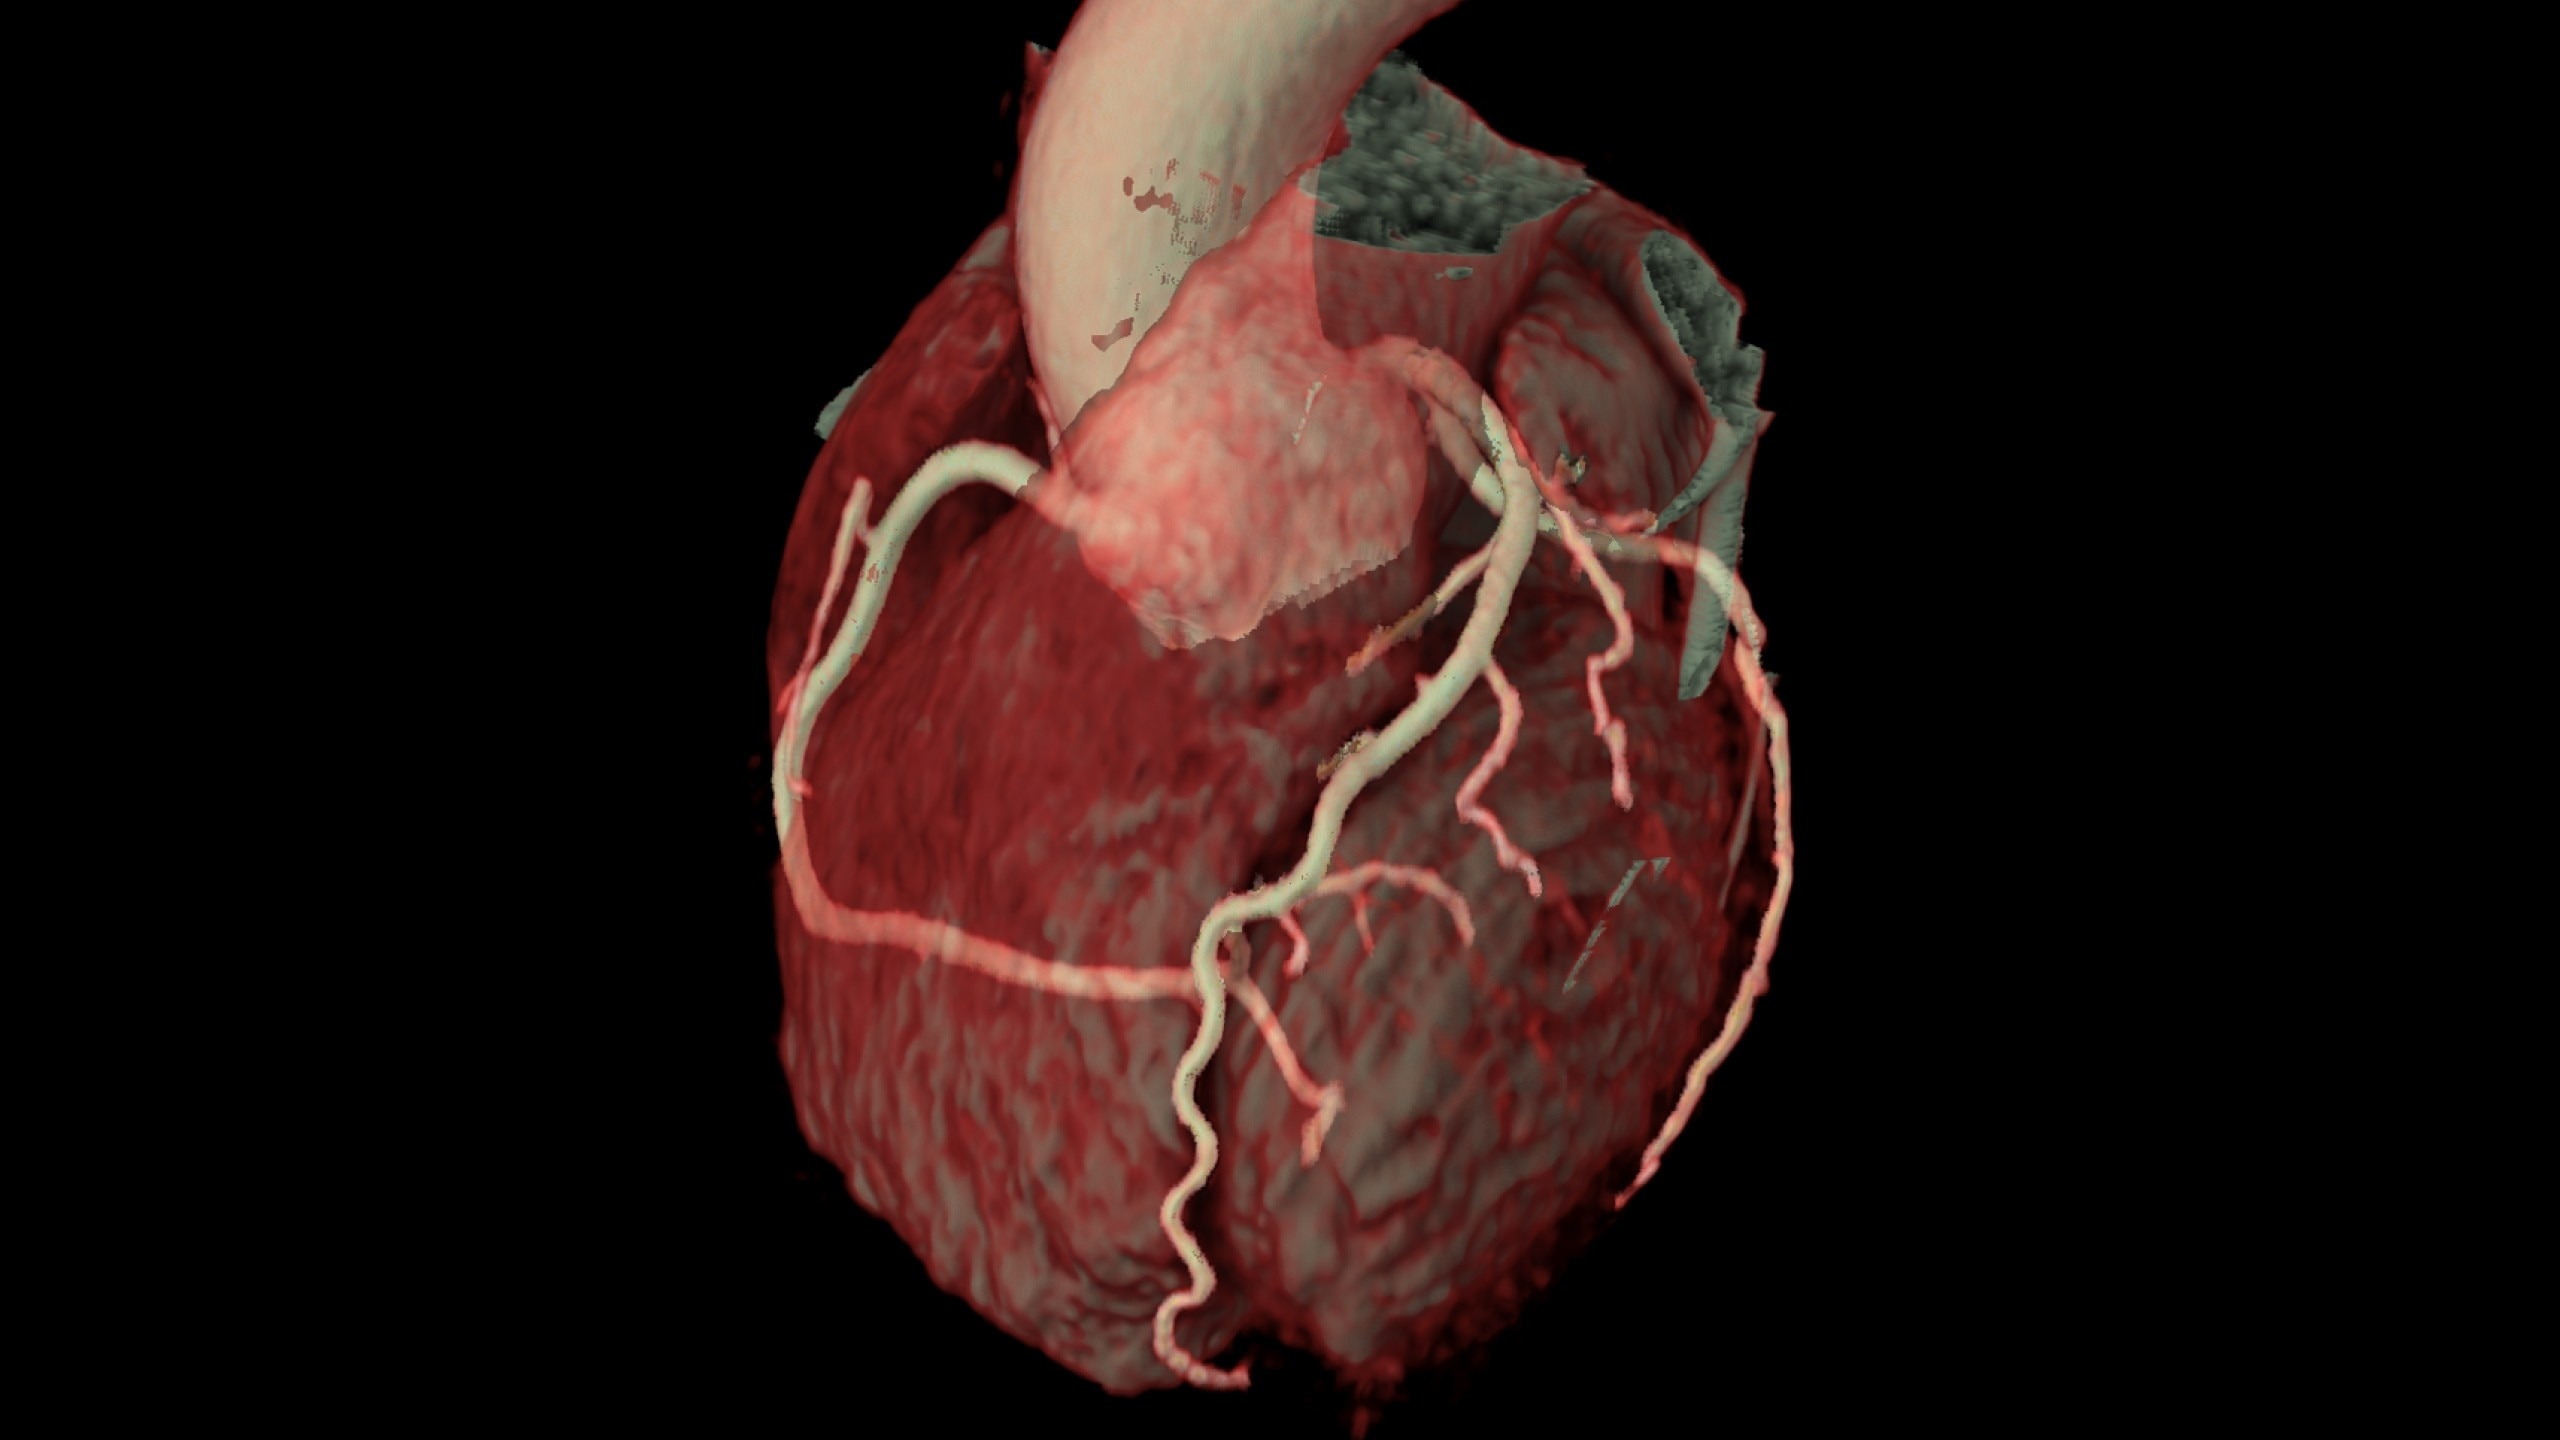

• Auto Coronary analysis automatically segments the

coronary tree, tracks and labels the coronary arteries

• Relative perfusion color codes and quantifies percent of

hypo-dense areas of myocardium with four selectable

color maps and fusion overlays with the coronary tree